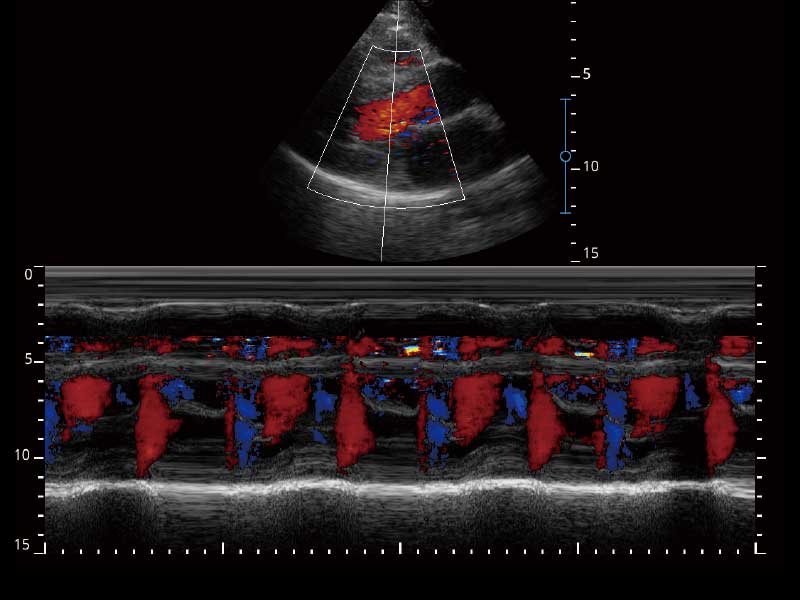

μ-Scan微米成像、空间复合成像、高分辨率血流成像。

PW自动包络分析,对血流动力学指数快速测量,自动生成结果,同时也支持可编辑的手动包络功能,对感兴趣区域进行单独分析,提高诊断准确率。